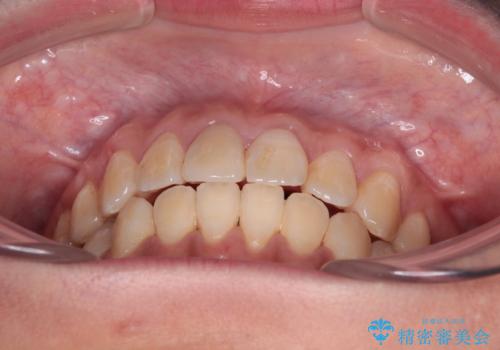

舌の突出癖による開咬と前歯の突出 インビザライン矯正治療

- 上下前歯の非接触と叢生を気にして来院された患者様です。

開咬の改善はインビザラインの最も得意とするところであるため、インビザラインを用いて矯正治療を行うこととしました。

治療開始直後に上顎前歯に激しい痛みが発現し、矯正治療を休んだり、マウスピースの装着時間を短くしたりと工夫をしましたが、残念ながら治療途中で失活していることが分かりました。

矯正治療の途中で前歯の根管治療とオールセラミッククラウンによる補綴治療を行い、その後インビザライン1セットを用いて細かい部分を仕上げました。